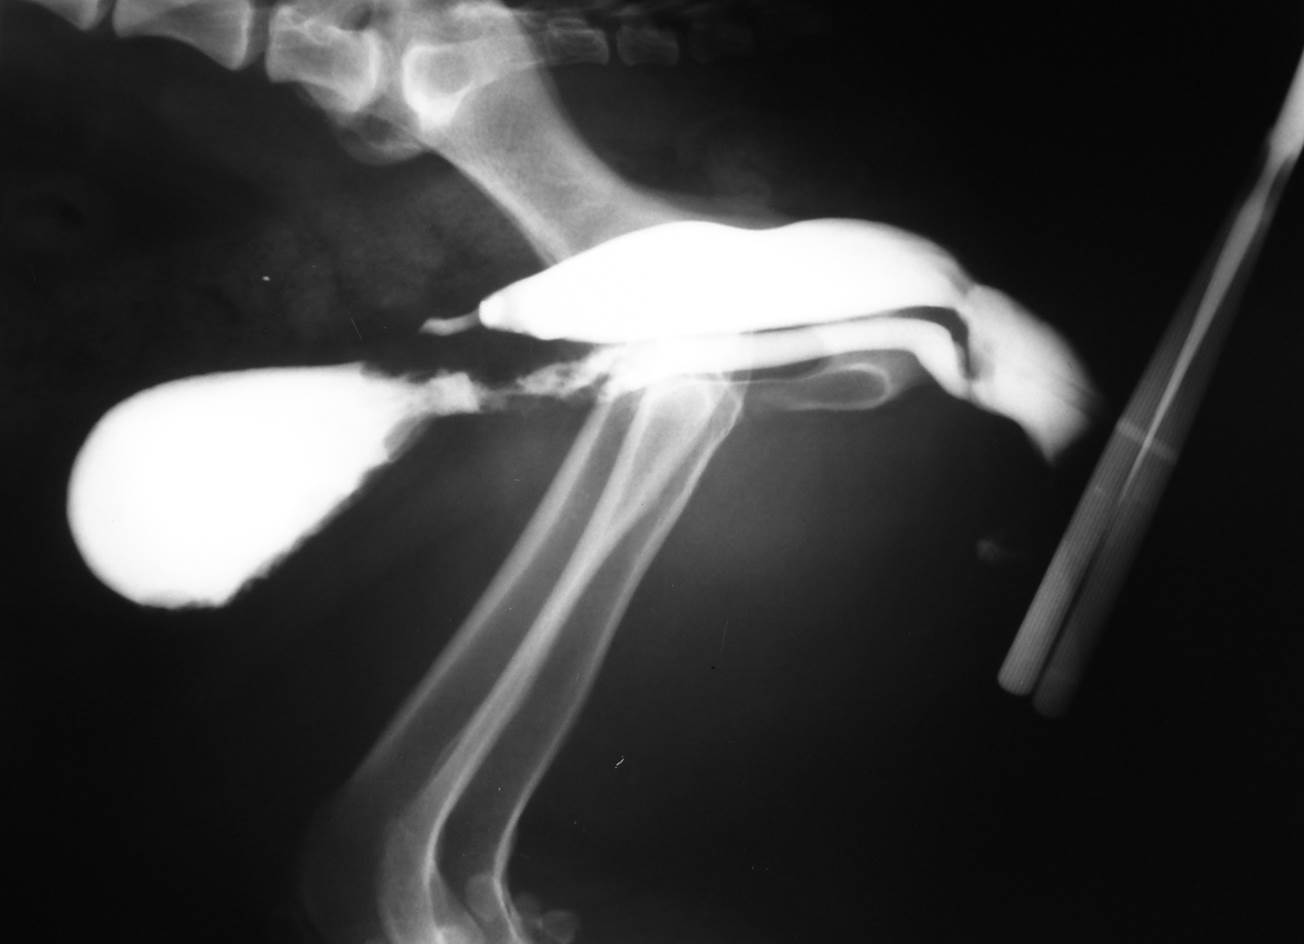

Case Lucky

Discuss this case?

–review clinical history with owners regarding further diagnostics

•eg ultrasound scan of the prostate?

–rectal exam to assess pelvic diaphragm

•uni or bilateral rupture?

–surgical repair